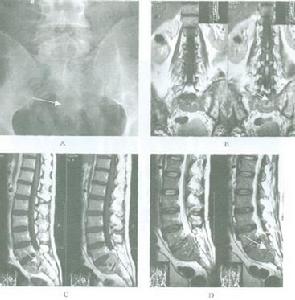

1.X線檢查 原發性骨淋巴瘤的X線表現多為溶骨性,“蟲噬樣”改變,在正常骨骼組織和病變組織之間有明顯的分界限,部分病人有骨皮質的破壞和缺損,但較少有骨膜反應還有部分病人表現為骨分離,即骨組織的正常部分與病變部分分離亦可表現為病理性骨折。

3.MRI 骨骼系統的病變為破骨性溶骨性、部分溶骨和部分硬化性及骨皮質的改變等多種表現。MRI對於原發性骨淋巴瘤的診斷敏感性較高,能發現其他檢查陰性的原發性骨淋巴瘤。同時它能發現周圍結締組織的病變。